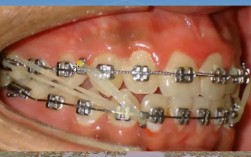

- 牙龈炎/牙周炎: 这是导致异常牙齿松动最常见的原因,矫正期间,如果口腔卫生维护不当(牙套本身就更难清洁),容易堆积食物残渣和牙菌斑,导致牙龈红肿、出血、发炎,甚至发展为牙周炎,牙周炎会破坏支撑牙齿的牙槽骨,导致牙齿松动、移位,甚至脱落。矫正期间和矫正后,牙周健康至关重要!

- 表现: 牙龈红肿、刷牙或吃东西时容易出血、牙龈萎缩、牙根暴露、口臭、牙周袋形成、牙齿松动度明显增大(超过生理范围)、牙齿移位(如出现“扇形”排列、牙缝变大)。